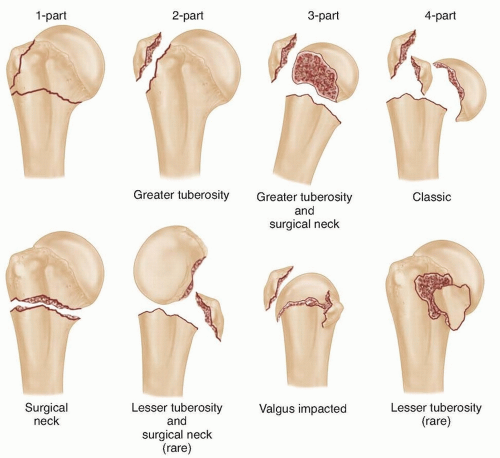

Классификация переломов диафиза бедренной кости: Иллюстрации и информация